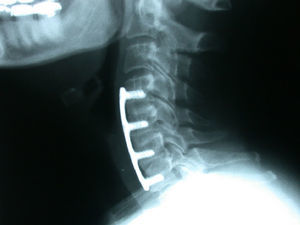

La fusión se consiguió en 18 pacientes (94%) del grupo de cresta ilíaca (fig. 1) y en 12 pacientes (71%) del grupo cajetín de PEEK-aloinjerto (fig. 2). Un paciente del grupo de cresta ilíaca (fig. 3) y 5 pacientes del grupo cajetín-aloinjerto desarrollaron seudoartrosis.

Cinco de los casos de seudoartrosis (uno del grupo de cresta ilíaca y 4 del grupo cajetín-aloinjerto) tuvieron un buen resultado clínico y uno regular (tabla 3).